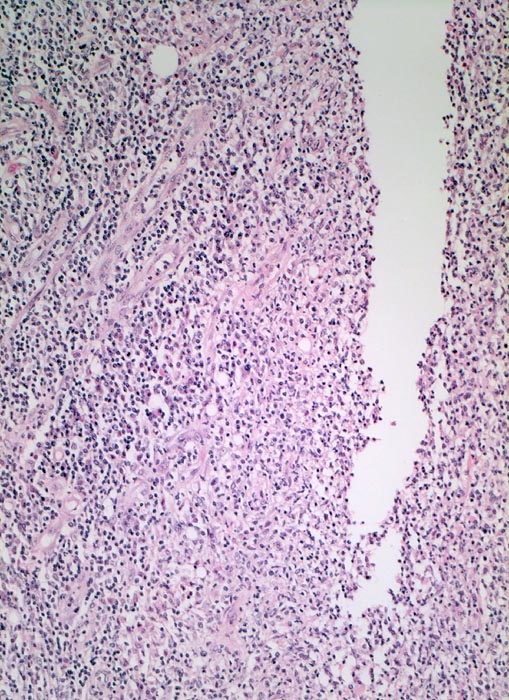

In Biopsien der Darmschleimhaut zeigen sich als Zeichen der Chronizität eine Architekturstörung, reepithelialisierte Schleimhautdefekte und metaplastische Veränderungen. Typisch für den Morbus Crohn sind entzündlich veränderte Schleimhautabschnitte neben weitgehend normaler Schleimhaut. In der Lamina propria findet sich ein verdichtetes gemischtes Infiltrat bestehend aus Lymphozyten, Plasmazellen, Makrophagen, neutrophilen und eosinophilen Granulozyten. Typisch für chronisch entzündliche Darmerkrankungen ist eine basal betonte Lymphoplasmozytose der Lamina propria. Die neutrophilen Granulozyten finden sich herdförmig in der Lamina propria, im Kryptenepithel (Kryptitis) und als Ansammlung in dilatierten Krypten (Kryptenabszess). Erhaltene Schleimhautabschnitte zwischen ulzerierten Arealen und Granulationsgewebe imponieren als entzündliche Pseudopolypen.

Befunde in der Mukosa wie epitheloidzellige Granulome, aphthöse Ulzera und Erosionen und fokal aktive Entzündung sind nicht spezifisch für den Morbus Crohn. Jene histologischen Aspekte, welche die Erkrankung am besten charakterisieren, sind in der Darmwand gelegen und lassen sich an einer endoskopisch gewonnenen Biopsie nicht nachweisen (fissurale, spaltförmige Ulzera, submukosales Ödem mit Lymphangiektasien, submukosale Fibrose, transmurale Entzündung mit lymphoidzelligen Aggregaten, neuromuskuläre Hypertrophie mit Wandverdickung (> 364), subseröse und submuköse Granulome (> 1133)).